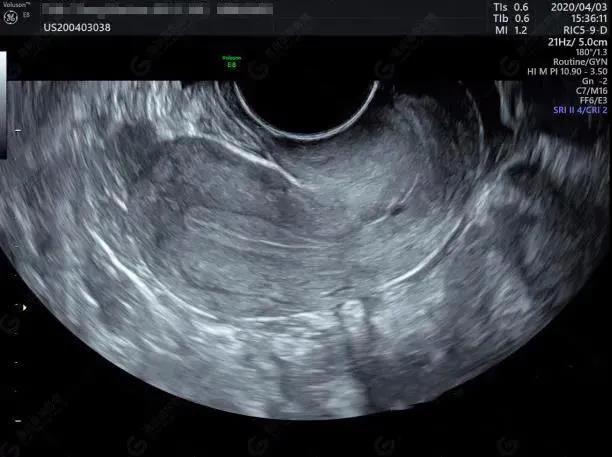

造影前常规检查

宫腔置管

子宫输卵管超声造影

长沙江湾妇产医院超声影像科团队运用GE-E10四维彩超,根据临床需求为患者制定个性化超声方案,可对包括子宫、输卵管、卵巢在内的女性生殖系统或盆腔相关的常见不孕原因进行系统性精准筛查,找出病因,对症治疗,并将其安全、无创、精准、便捷、经济的特点发挥到极致!